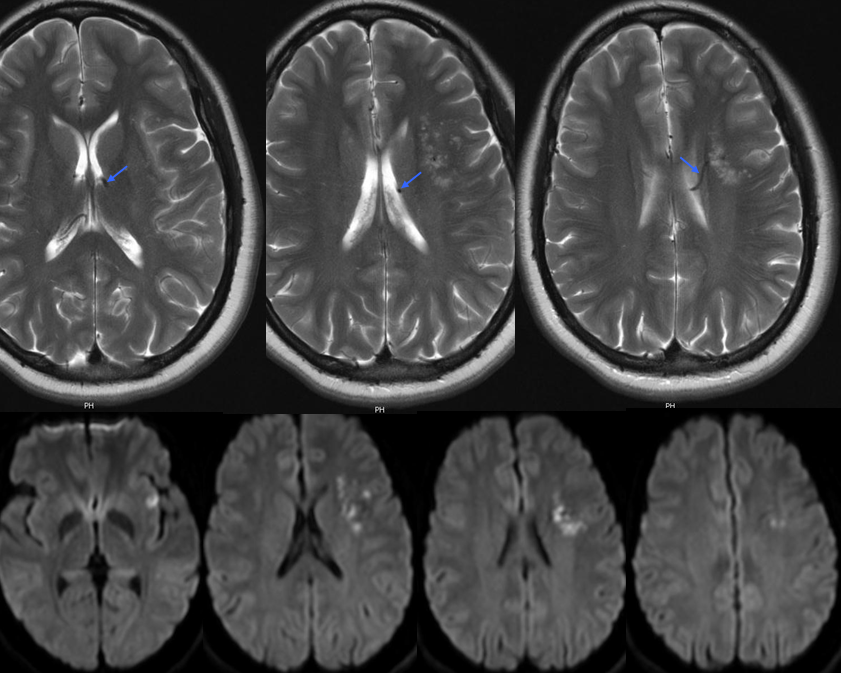

МРТ головного мозга: показания и результаты

Раздел: Визуальный дайджест